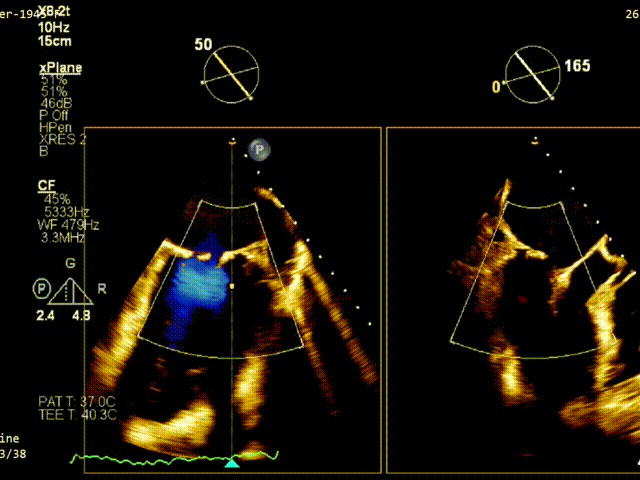

术前TEE评估

经食道超声提示,患者二尖瓣P1 commissural脱垂、腱索断裂合并重度反流(Carpentier II型/DMR4+)。

二尖瓣后瓣环明显钙化;主动脉瓣轻度钙化;三尖瓣中度功能性反流(FTR2+)。左房明显扩大;左室壁非对称性肥厚,以室间隔基底段肥厚为著(HOCM)。左室整体收缩功能正常。

二尖瓣环AP径33mm,二尖瓣后瓣环明显钙化,房间隔拟穿刺高度40mm;二尖辦脱垂宽度5.7mm,脱垂高度7.7mm,二尖瓣1区前叶长度29mm,后叶长度19mm,二尖瓣2区前叶长度23mm,后叶长度14mm,MVA=4.0cm²。

术前1区X-Plane反流情况